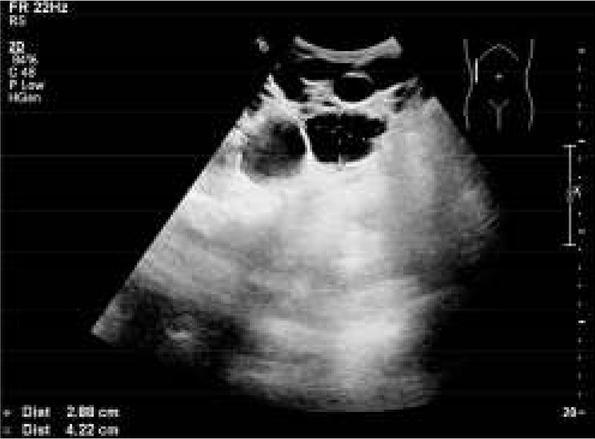

The boy was born at term, from the first pregnancy and delivery with a birth weight of 3800g, and 10 points on the Apgar score. The perinatal period was normal. The family history revealed ADPKD in the grandfather and the grandfather’s sister, who both died because of end-stage renal disease (ESRD) at the age of 62 and 65 years, respectively. ADPKD was also diagnosed in the child’s mother at the age of 18 years. At the age of 6 years, the patient was diagnosed with a murmur in the heart. Echocardiography was performed and it showed mitral valve prolapse. The electrocardiogram (ECG) and chest X-ray were normal. Ultrasonography (US) of the abdomen was performed for the first time at the age of 12 years, at the request of the mother. US revealed left renal agenesis, hypertrophy of the right kidney with 129 mm in diameter and two cysts 5-6mm in diameter. On the US pyelocalyceal system, the bladder, liver, spleen, and pancreas were normal. The child was admitted to the Nephrology Department for diagnosis and treatment. Physical examination revealed no abnormalities, blood pressure (BP) and ophtalmoscopic examination were normal. Normal kidney function was found based on laboratory tests: urea-27 mg/dl (normal range 17-45 mg/dl), creatinine-0.6 mg/dl (normal range 0.2-0.7 mg/dl), glomerular filtration rate (GFR) was 109 ml/min/1.73m2 (normal range 90-120 ml/min/1.73m2), urinalysis was normal. Static scintigraphy (DMSA) showed left renal agenesis, and hypertrophy of the right kidney with normal function. Voiding cystourethography ruled out vesicoureteral reflux. The boy was followed up in an outpatient clinic. At the age of 18 years, his physical development was normal: height 178 cm (50-75 percentile), weight 72 kg (75-90 percentile), BP 125-130/65-70 mmHg, in ambulatory pressure monitoring (ABPM) mean systolic (SBP) and diastolic (DBP) blood pressure was on the 50th percentile for sex, and height, BP load and BP circadian profile were normal, with overnight drop of BP, with MAP 10%, SBP 13%, DBP 15% (normal value ≥ 10% ). Laboratory tests were as follows: urea-25.6 mg/dl, creatinine-1.0 mg/dl, GFR 97.9 ml/min/1,73m2, isotopic creatinine clearance (Tc-99mDTPA) 99 ml/min/1.73m2, normal urinalysis, albuminuria below 20 mg/a day. US of the abdomen showed hypertrophy of the right kidney with 138 mm in diameter and many cysts up to 40 mm in diameter. Liver, spleen and pancreas were normal (fig. 1).

Ultrasonography shows right kidney with many cysts up to 42 mm in diameter.